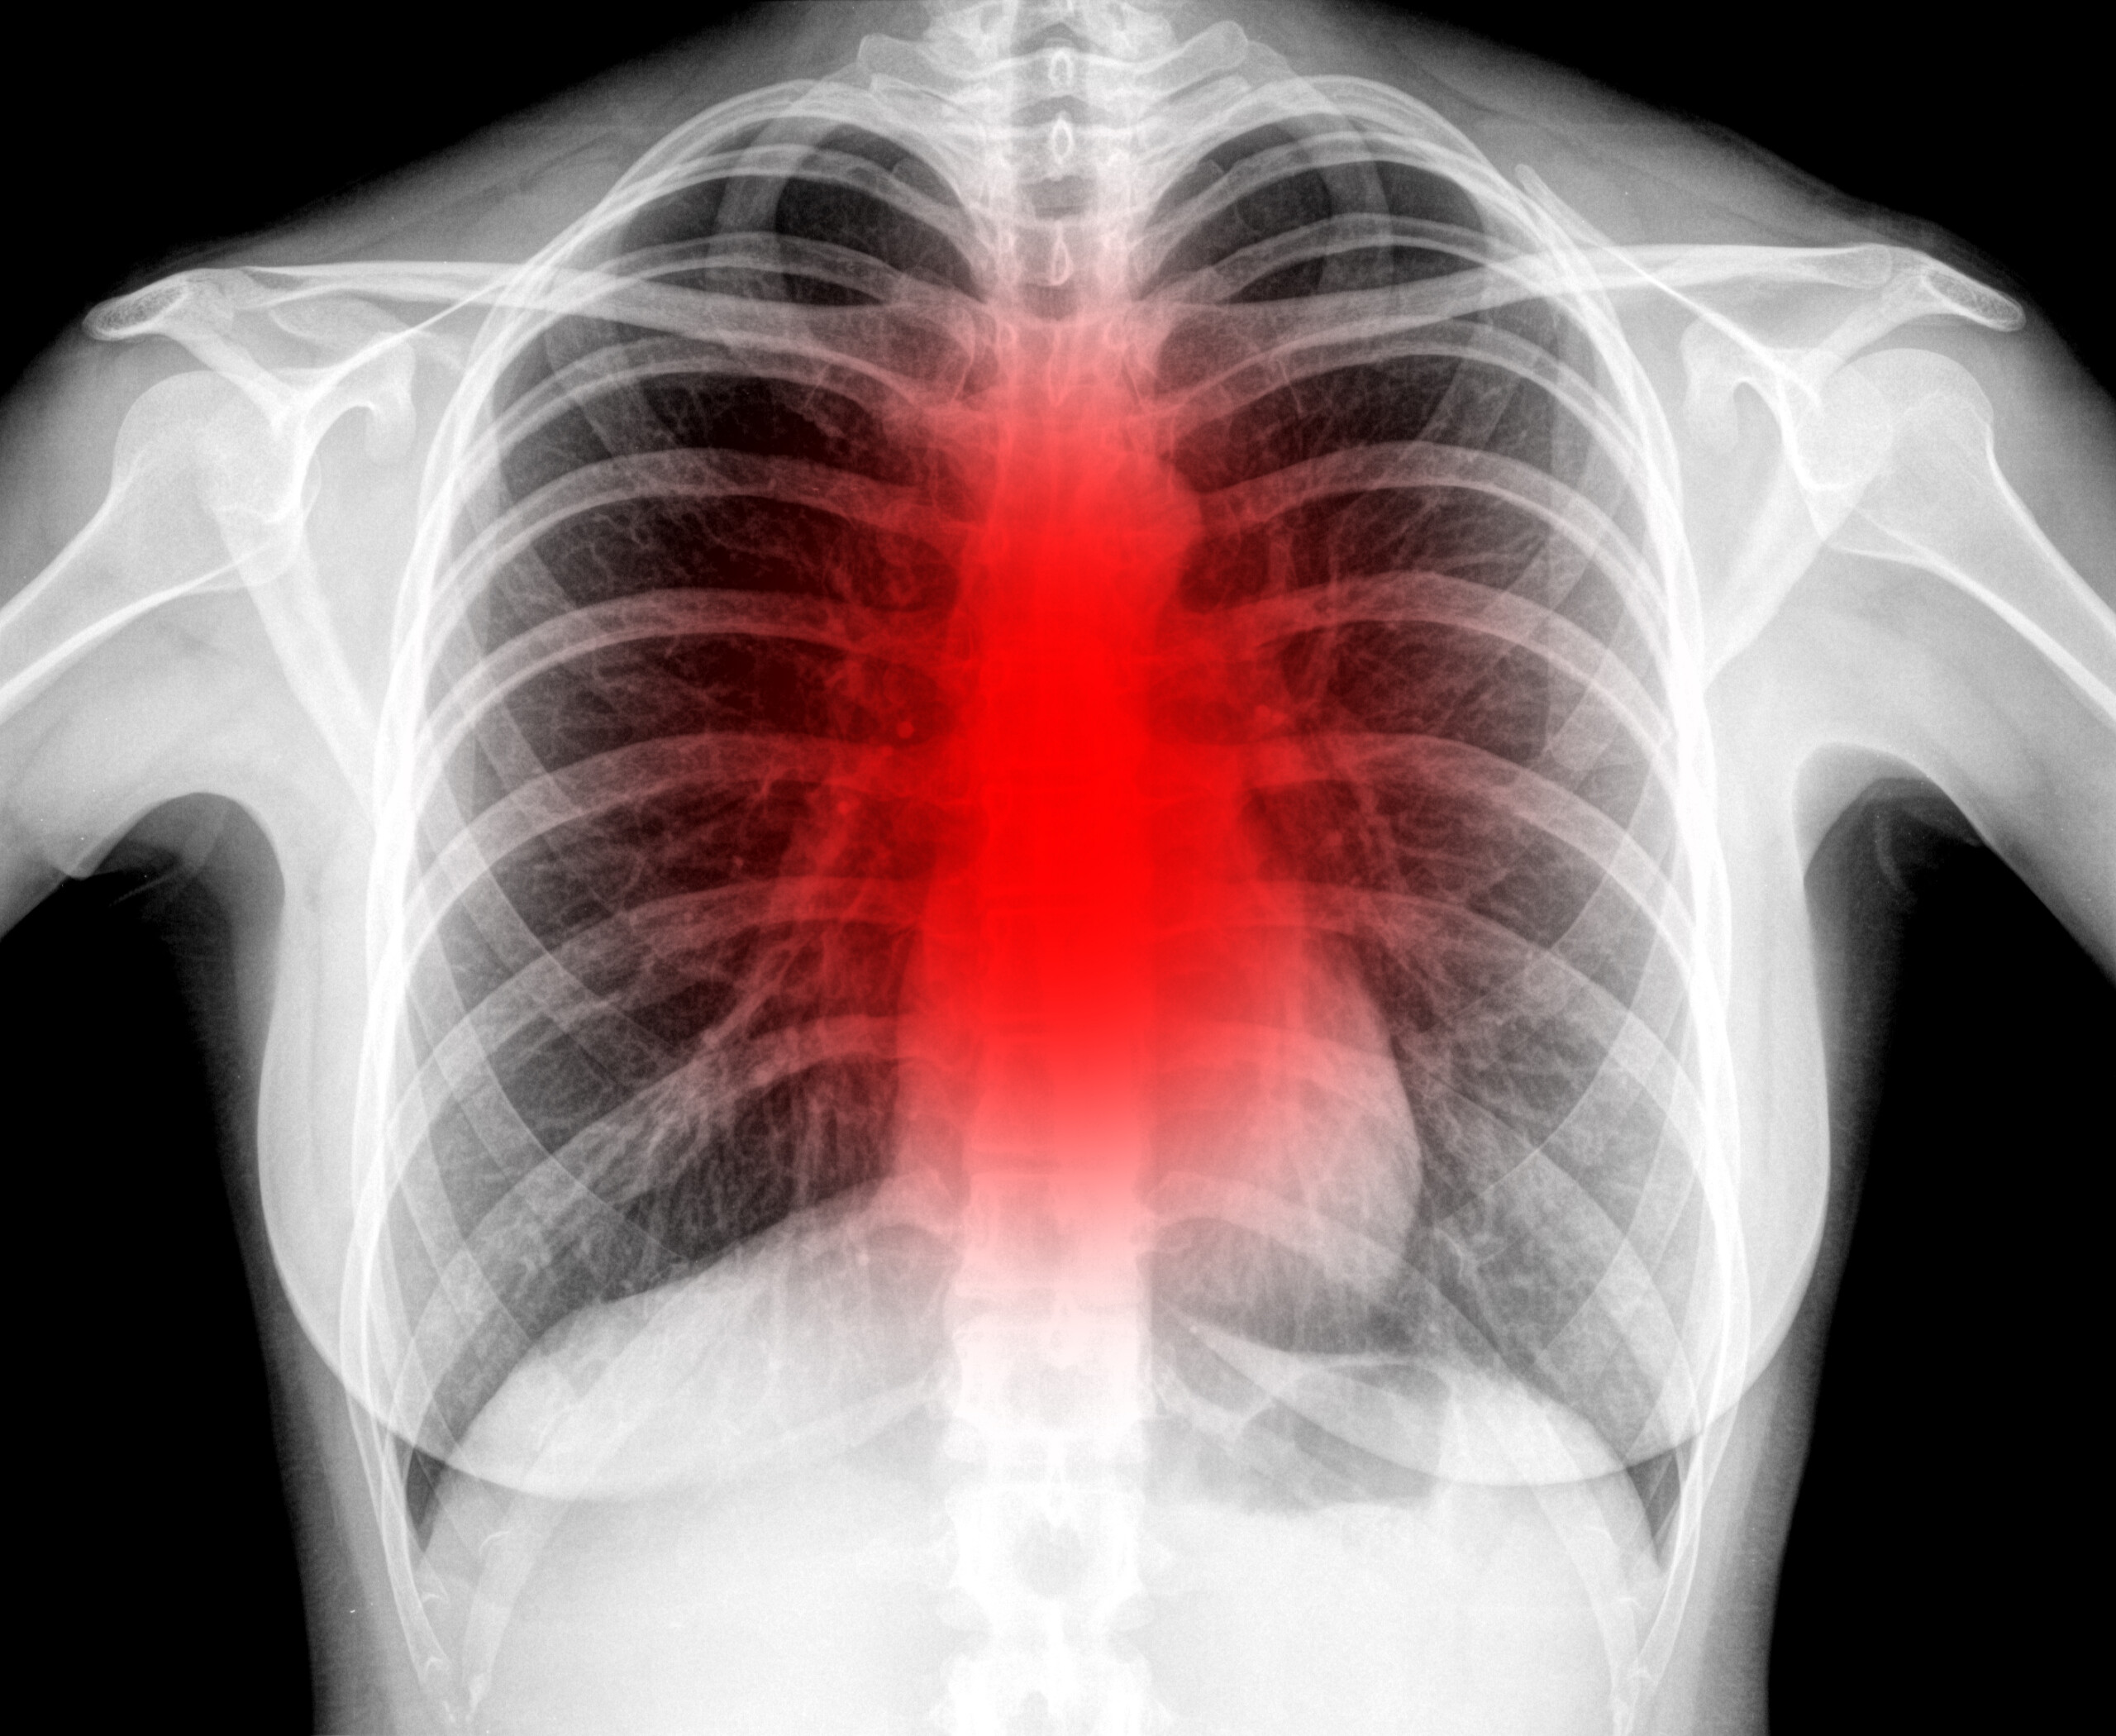

그런데 2, 30대라 할지도 코로나 조심하셔야겠습니다. 젊은 층이 코로나로 사망하는 경우가 적을지는 몰라도, 영구 후유증을 까지 피해갈 수는 없습니다. 한번 코로나19에 걸리면 평생 폐병이나 단기기억상실증 등을 떠안고 죽을때까지 살아야 할지도 모른다는 것입니다.

앞선 완치자들의 증언을 바탕으로 정리해보면 1) 호흡 문제, 2) 기억력 감퇴, 3) 언어 능력 저하, 4) 만성 피로 등의 코로나19 후유증이 존재하는 것으로 보입니다.

젊은 층이라 할지라도 코로나 바이러스에 감염될 시 지독한 고통을 겪는다고 합니다. 하지만 고통은 한순간이고 이겨내면 그만이지만 후유증은 오래 남습니다. 후유증에 영원히 시달리게 될지도 모릅니다. 그말인즉, 코로나에 일단 걸리면 예전의 그 건강하던 몸상태로 돌아갈 수 없을지도 모른다는 것입니다.